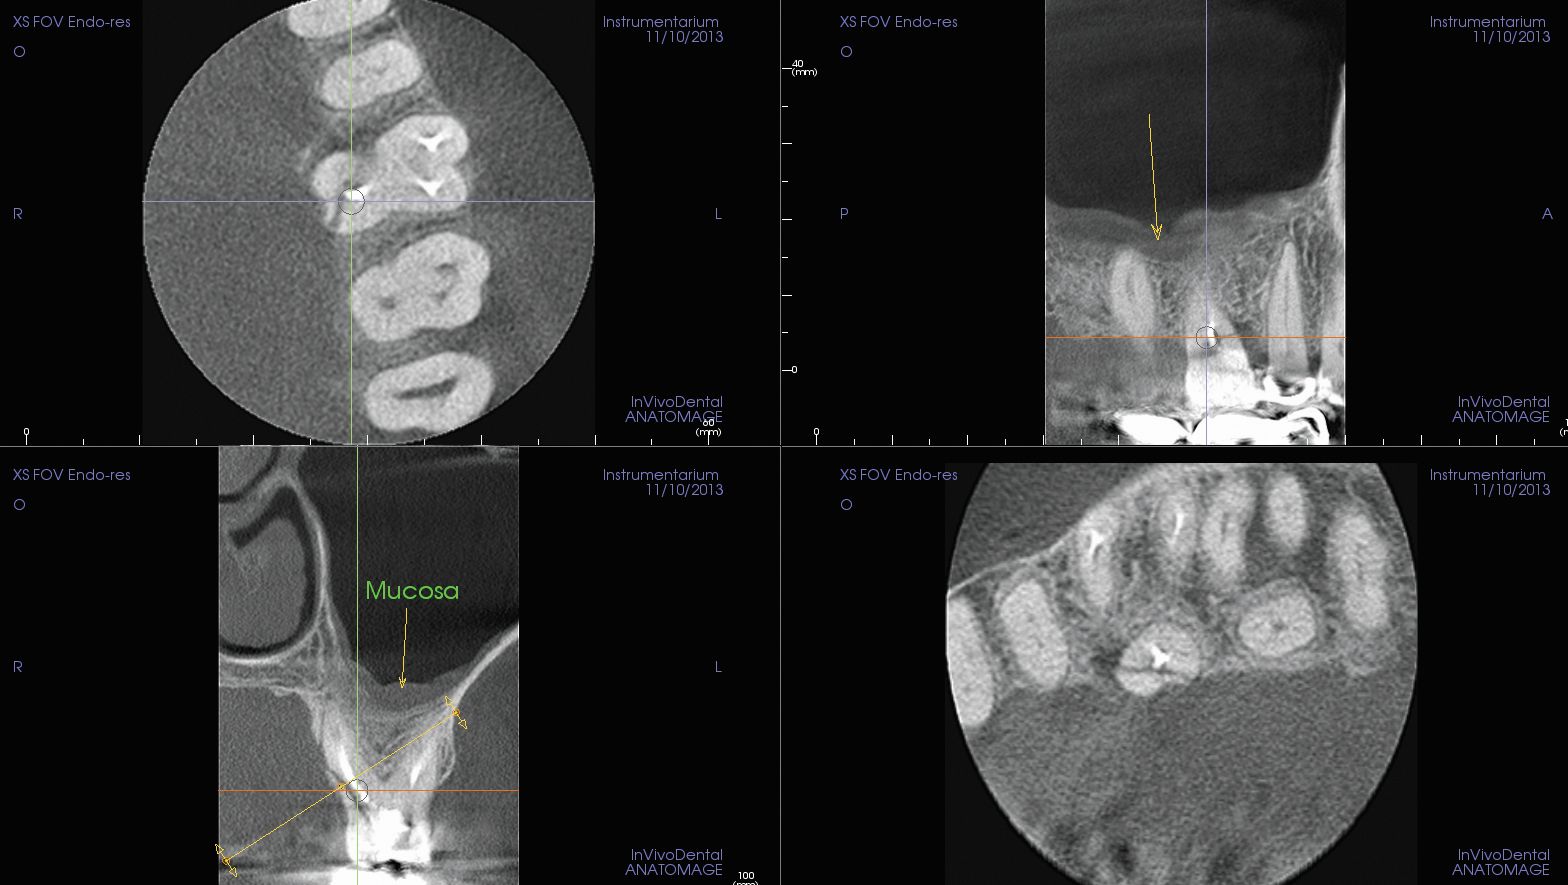

… Identify Root Fractures

OP300 Maxio features a high-resolution modality to take highly detailed 5x5 cm 3D scans, the ideal support for the most complex endodontic cases. OP300 Maxio helps visualize small anatomical details like fractures and endodontic root fillings.

In addition the Metal Artifact Reduction (MAR) technology reduces the amount of glare produces by metal or opaque objects producing crisp views of the anatomical region of interest.